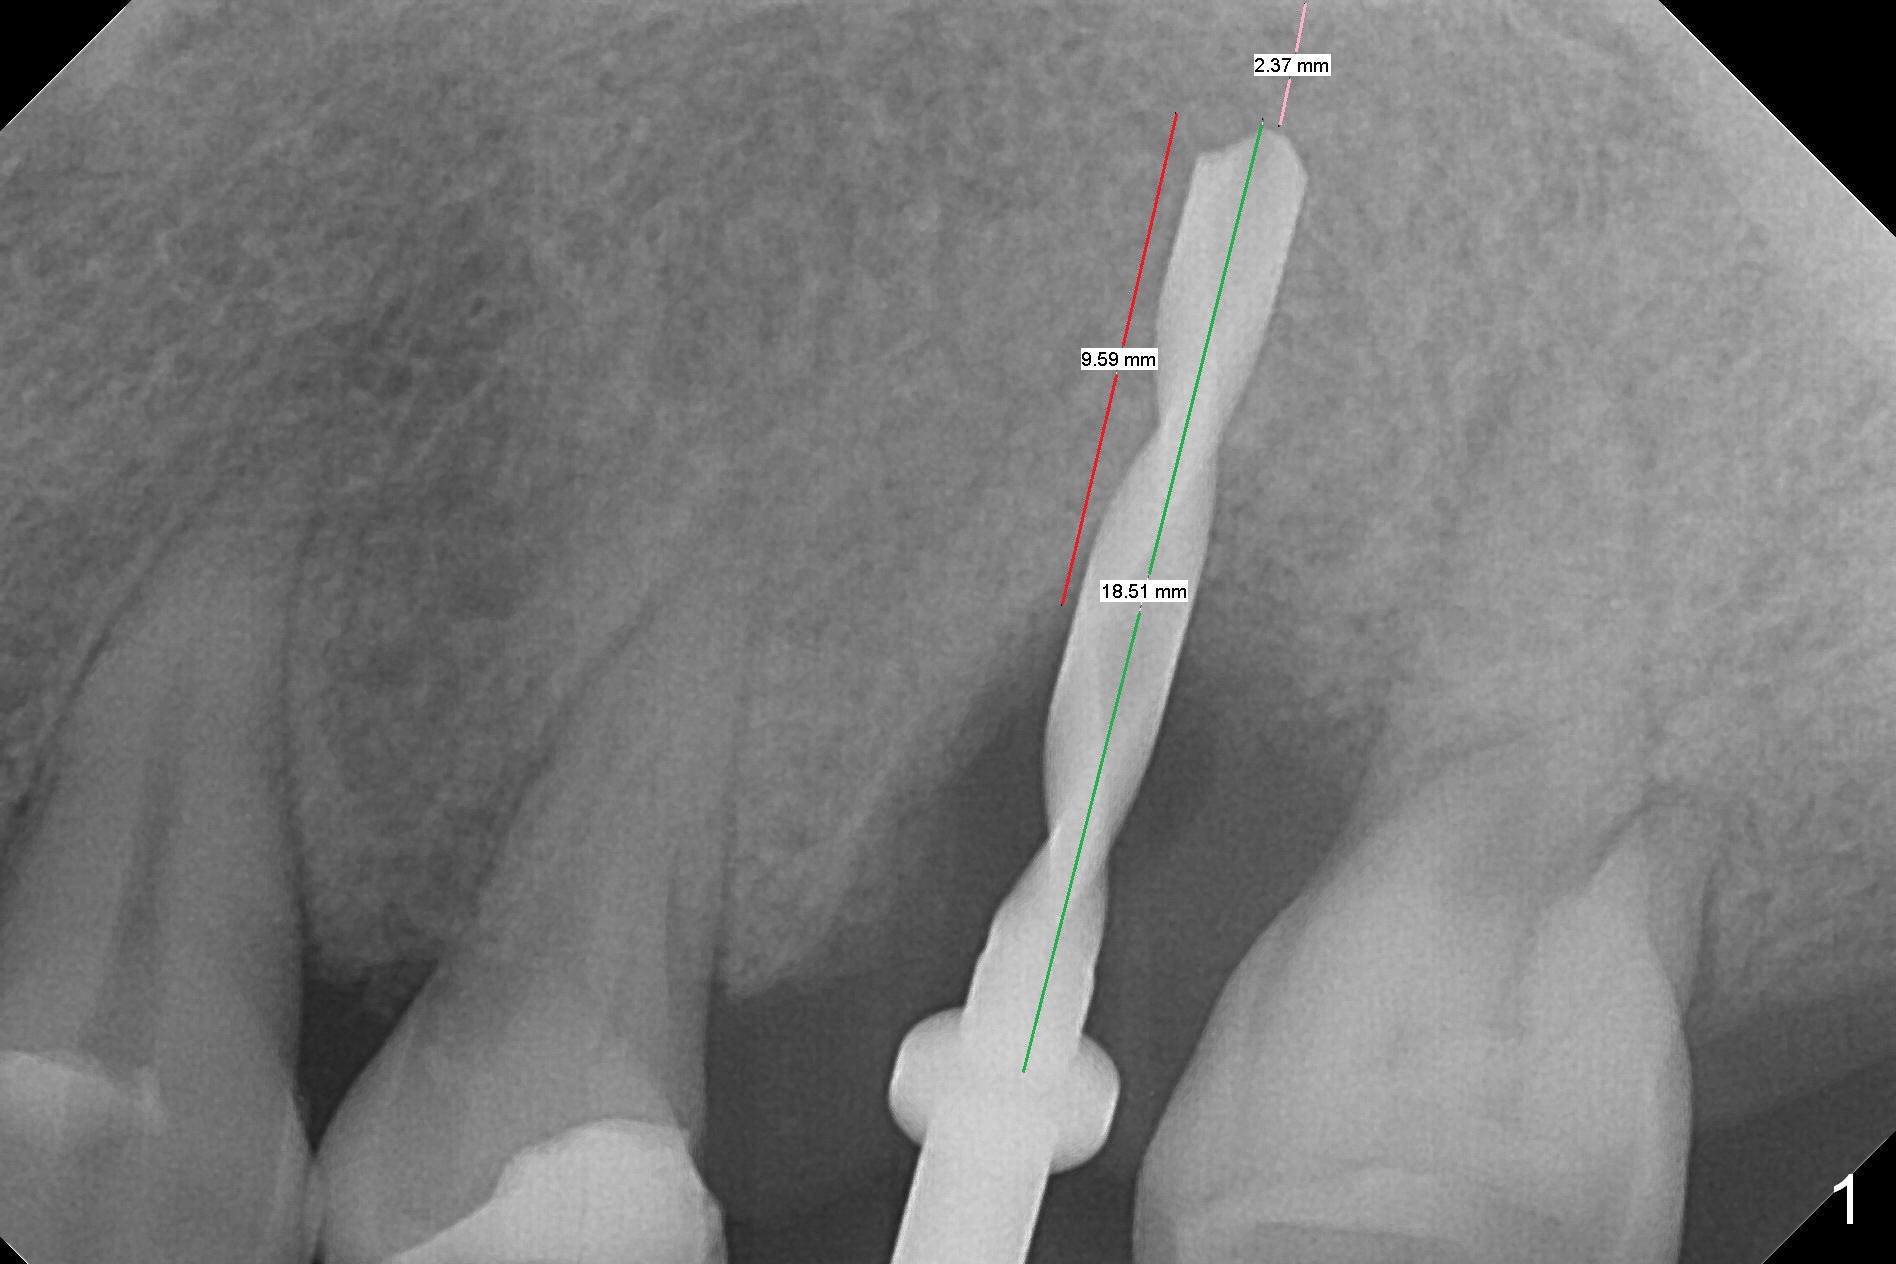

Initial osteotomy depth is 18 mm (Fig.1 green line) with 9 mm in the native bone (red line).  The bone density feels to be low.  There is at least 2 more mm bone apically (pink line).  The depth is increased by 2 mm so that when a 3.8x15 mm implant is placed, there is 10-11 mm implant/bone contact (Fig.2 red line).  There is large bony defect (Fig.3 *), which is bone grafted (Fig.4 *).  Finally a longer abutment is placed (4.5x5.5(5) in Fig.4 vs. 4.5x4(5) in Fig.2,3).  The 5 mm cuff does not look too long buccally (Fig.5) or palatally (Fig.6).   To prevent postop buccal gingival overgrowth (2), the buccal margin of an immediate provisional is subgingival (Fig.7-9 *).  Bone density between #13 and 14 appears to increase 3 months postop (Fig.10).  The implant seems to be equi-crestal (Fig.11 ^).  There seems to be more bone growth (i.e., decreasing gap) 6 months postop (Fig.12).  Impression is taken.  A crown is delivered nearly 7 months postop (08/07/2017).   While there is minimal bone loss at #13 and 15 three years and 4 months post cementation, the tooth #14 and 18 are mobile (Fig.13,14).